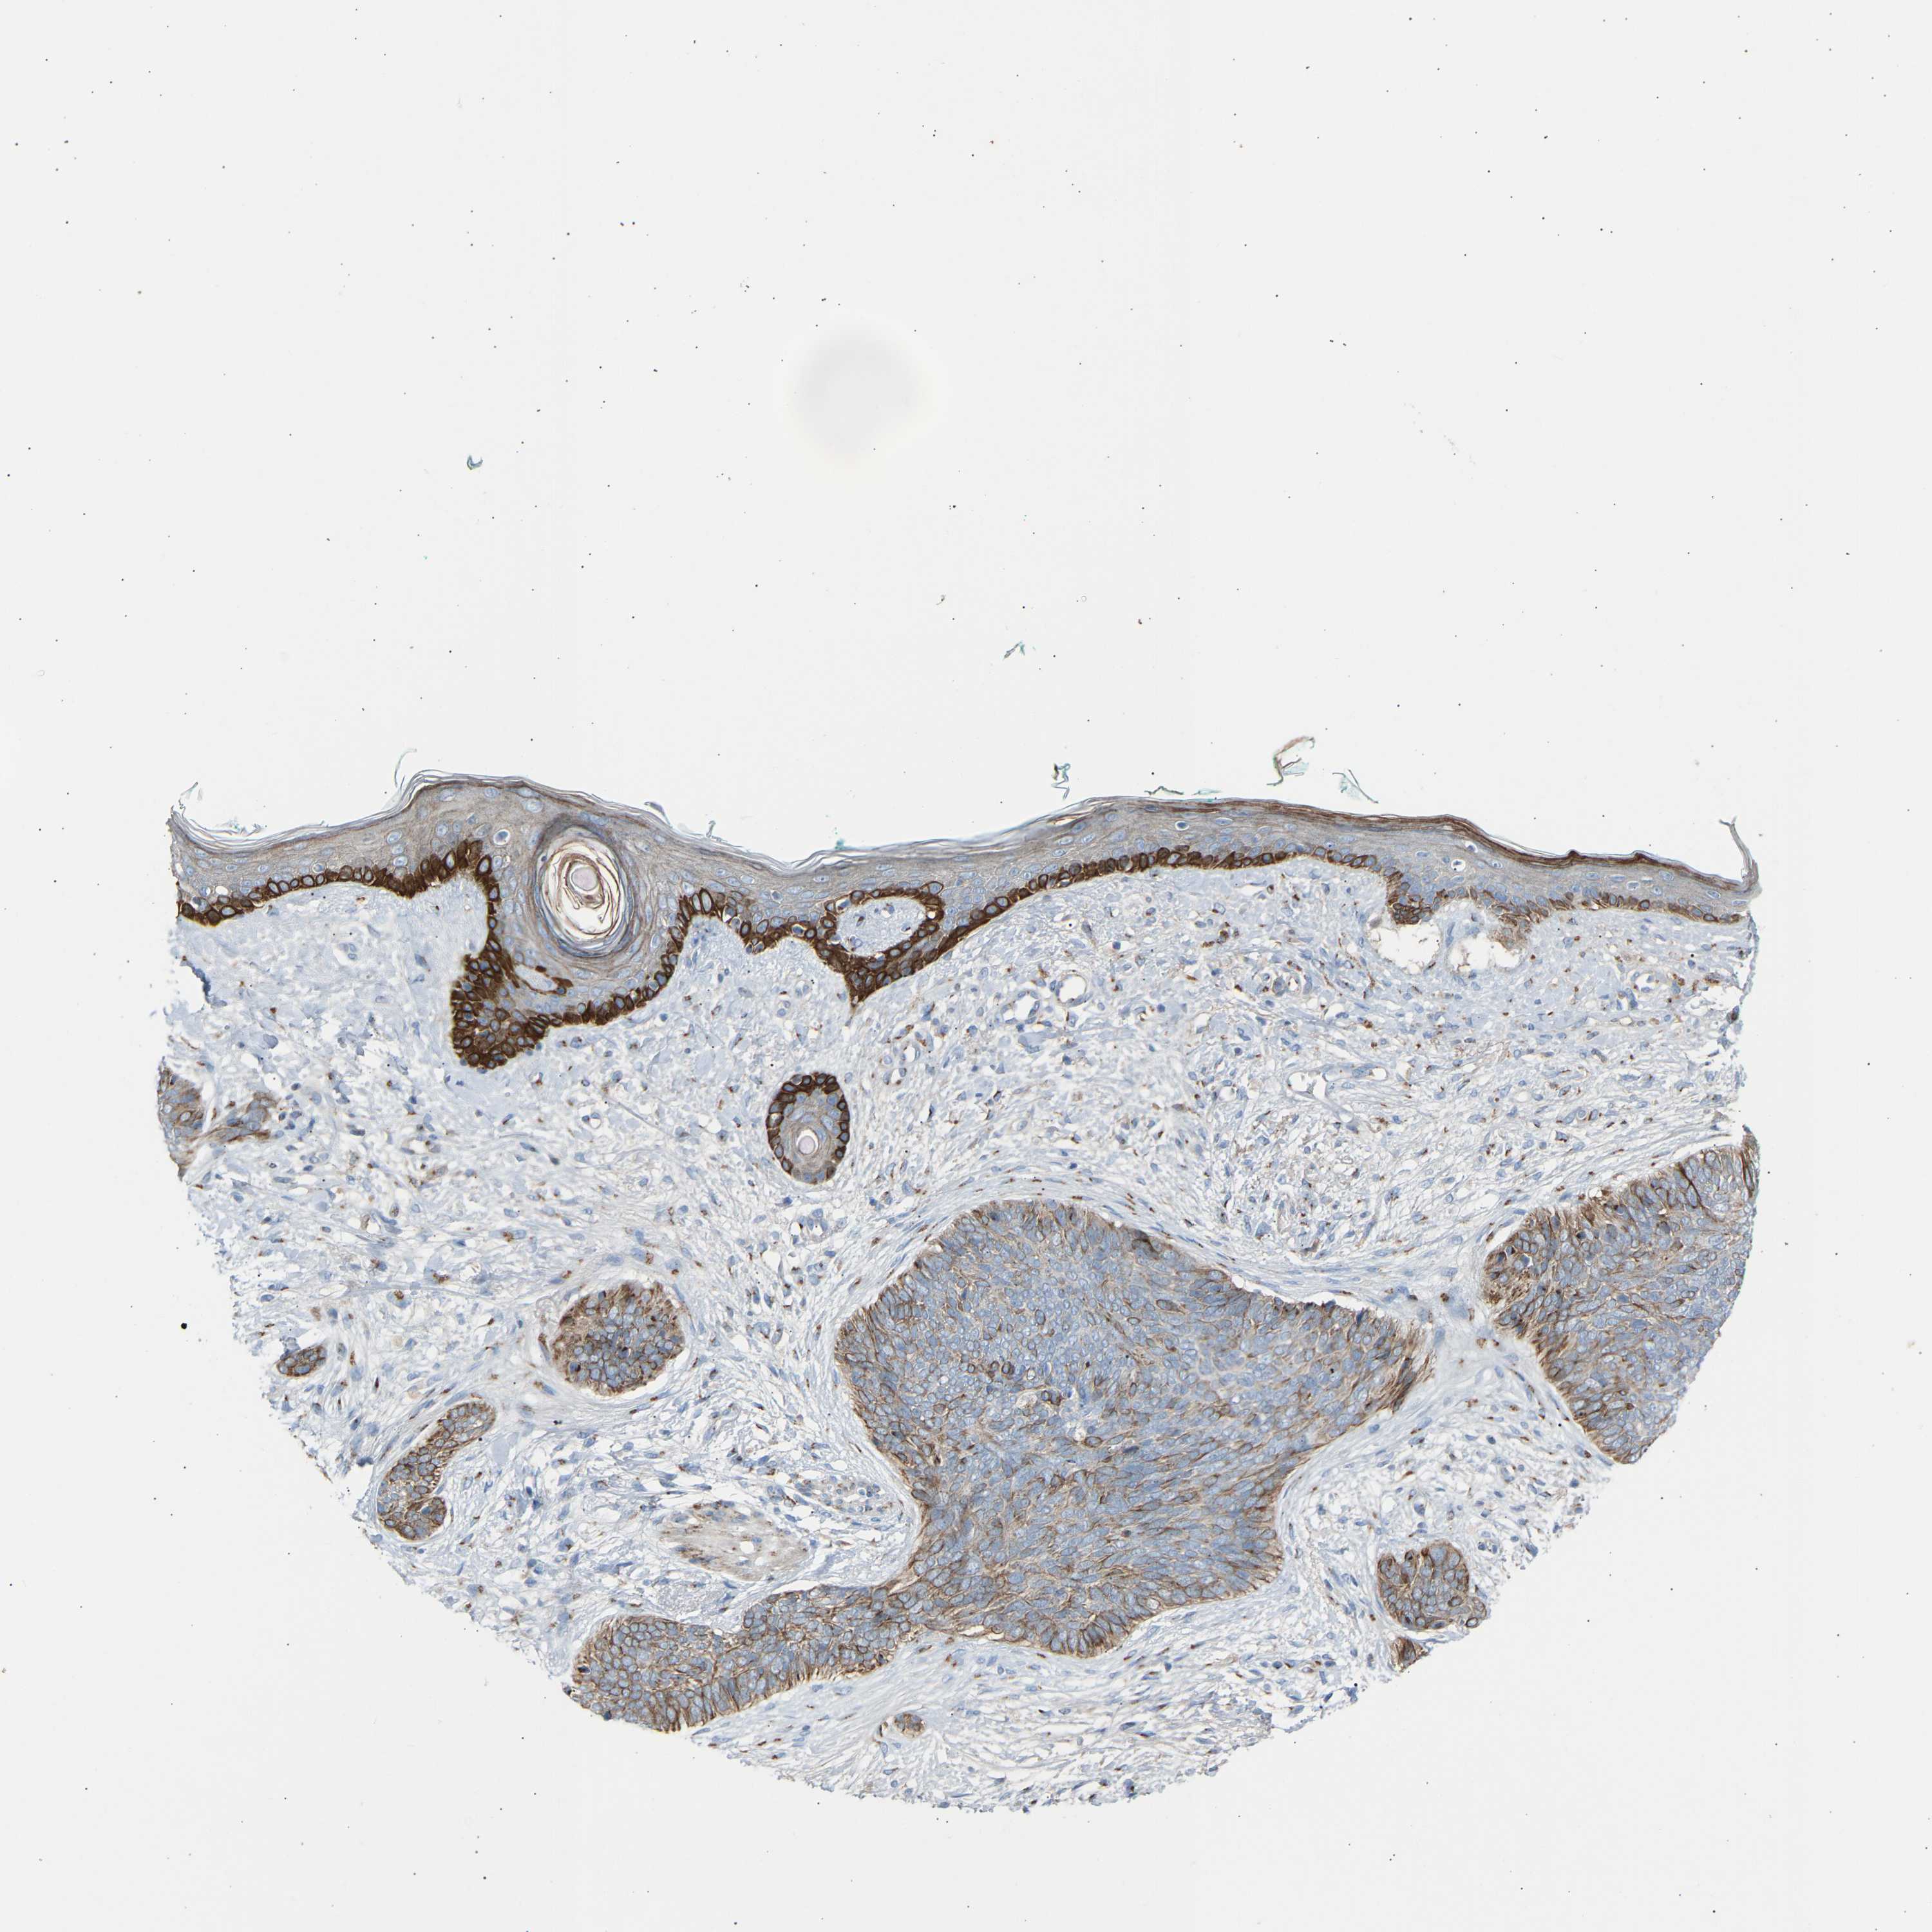

Basal cell and squamous cell cancer

SKIN CANCER - Protein expressioni

A mouse-over function shows sample information and annotation data. Click on an image to view it in a full screen mode. Samples can be filtered based on level of antibody staining by selecting one or several of the following categories: high, medium, low and not detected. The assay and annotation is described here.

Antibody stainingi

Antibody staining in the annotated cell types in the current human tissue is reported as not detected, low, medium, or high, based on conventional immunohistochemistry profiling in selected tissues. This score is based on the combination of the staining intensity and fraction of stained cells.

Each image is clickable and will lead to virtual microscopy that enables deeper exploration of all samples and also displays staining intensity scores, fraction scores and subcellular localization as well as patient and tissue information for each sample.

Antibody HPA020060

Staining

High

Medium

Low

Not detected

Intensity

Strong

Moderate

Weak

Negative

Quantity

>75%

75%-25%

<25%

None

Location

Nuclear

Cytoplasmic/membranous

Cytoplasmic/membranous,nuclear

Basal cell carcinoma